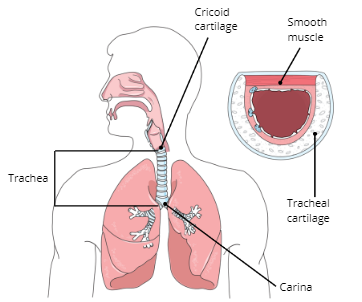

Cricoid Cartilage

Trachea

Carina

Function of Trachea